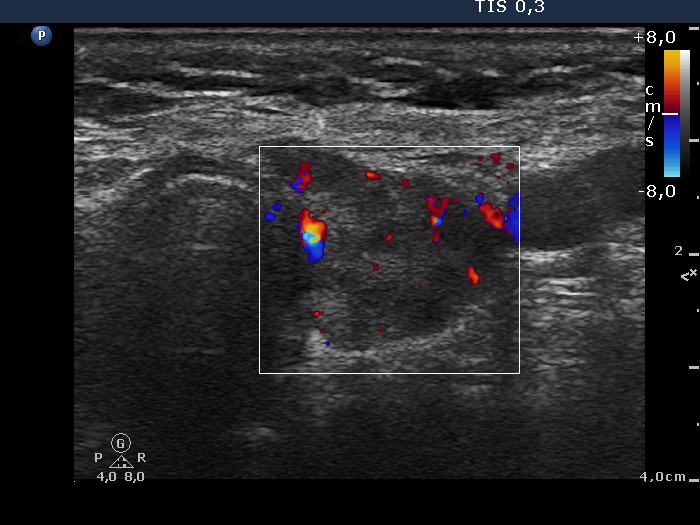

Lymphocytic thyroiditis - case 897

Examination one

Six month later

Focal form of lymphocytic thyroiditis is presented. At the first examination, beside smaller hypoechoic areas, the left lobe had a larger discrete lesion. It was doubtful whether this should be regarded as pathological nodule or not. In the first case, the lesion is an EU-TIRADS 5 nodule due to the irregular margins while in the latter, this is an EU-TIRADS 1 lesion. Six months later, the lesion had virtually disappeared which means that this was not a true nodule.